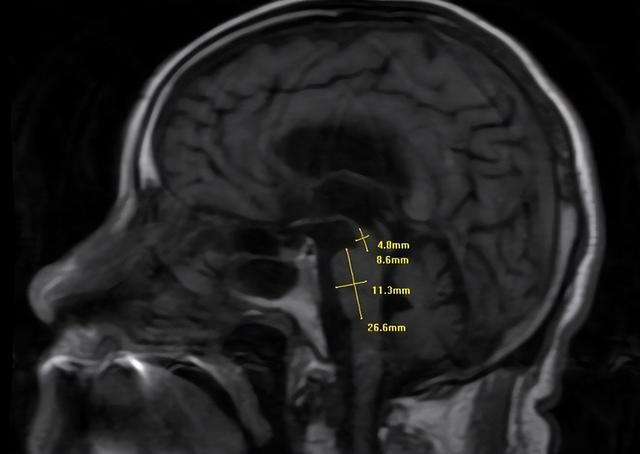

近日,陕西省核工业二一五医院神经内科团队通过一张头部核磁共振影像,成功为一位83岁、多次莫名跌倒并伴随吞咽说话困难的老人明确了病因——进行性核上性麻痹(PSP)。该病在影像上表现为中脑萎缩形成的“蜂鸟征”,是一种极易被误诊的神经系统退行性疾病。

随后,脑部核磁共振影像证实了诊断:患者中脑明显萎缩,侧影形似一只“蜂鸟”。这正是PSP的特征性表现——“蜂鸟征”。该病目前尚无根治方法,主要以对症支持、康复护理为主,但明确诊断能帮助患者及家属停止盲目求医,进行针对性康复与管理,预防跌倒骨折、吸入性肺炎等并发症,有效提升生活质量。